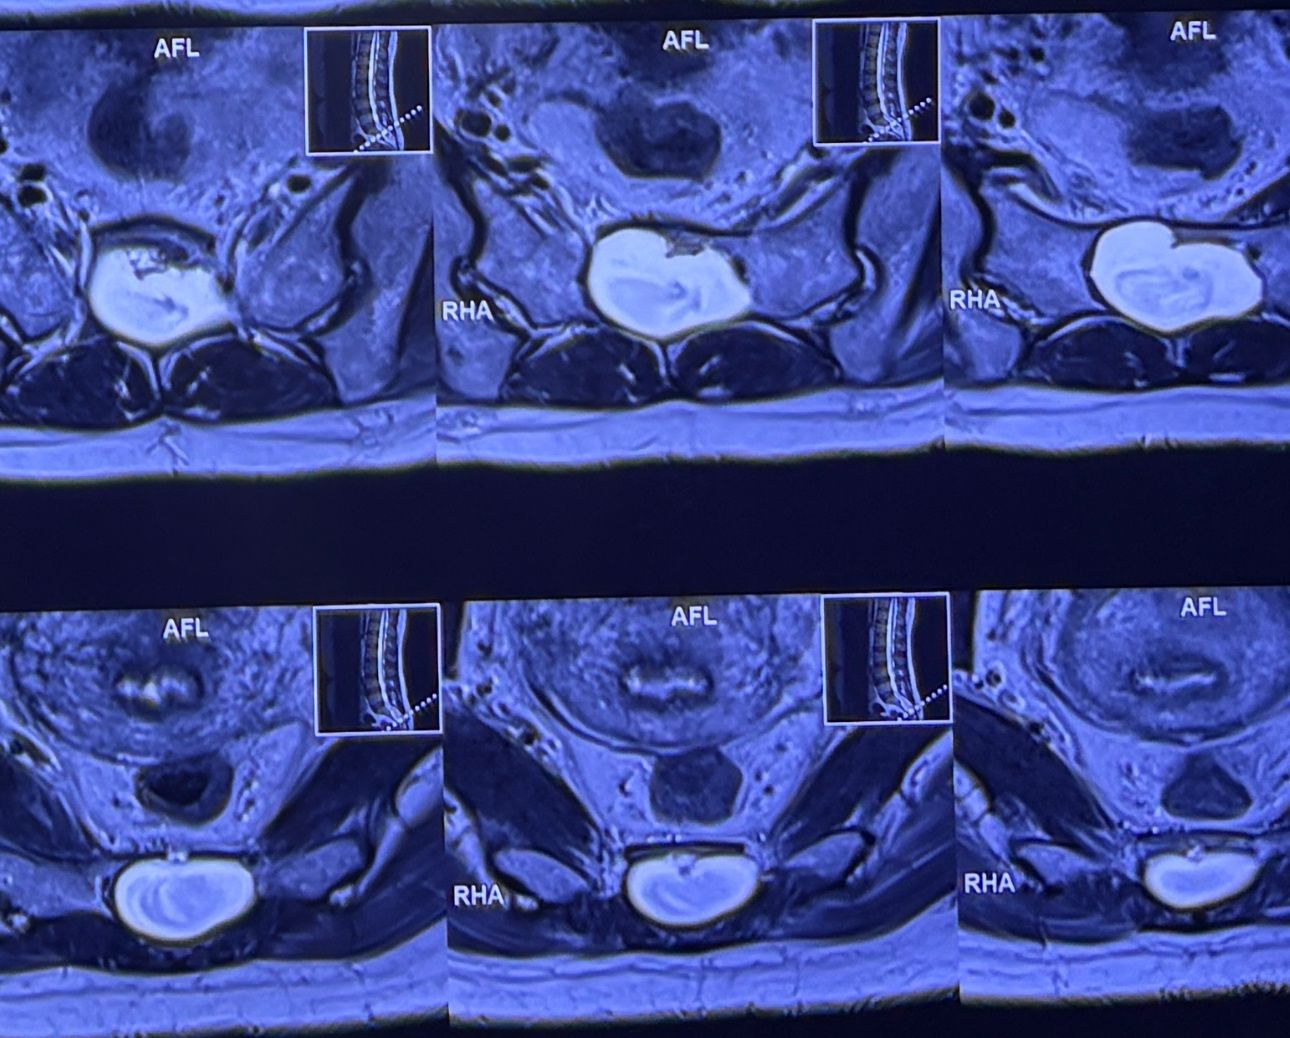

60 years old female patient presented to my clinic today,

May 31/2025 with R. Chronic pelvic pain which gets aggravated by walking. Her lower extremity motors all were fine

She has had chronic neck pain as well with radiation to R Upper extremity

I would like to show especially to new grads some information and improve their x ray and mri readings

Would be so great to hear from chiropractic doctors or any other specialist other findings we may have missed

Findings:

L4-L5 level:

sever L4-5 canal stenosis mainly due to FL hypertrophy?

CSF block. Mild L3 retrolisthesis, facets hypertrophy bilateraly causing L and R IVF stenosis, disc hyperbule

Since I’ve noticed instability in some segments I asked for dynamic L/S x ray:we see mild L4 ant listens due to DjD/DDD. There is not any pars defect.

In cervical mri I marked some findings plus their reports

I will give her treatment via Cox chiropractic flex dis and axial decompression. I would use DTS decompression

Since there is a few mild to moderate DjDs/ DDs in her lower back I won’t use lumbar adjustment on her